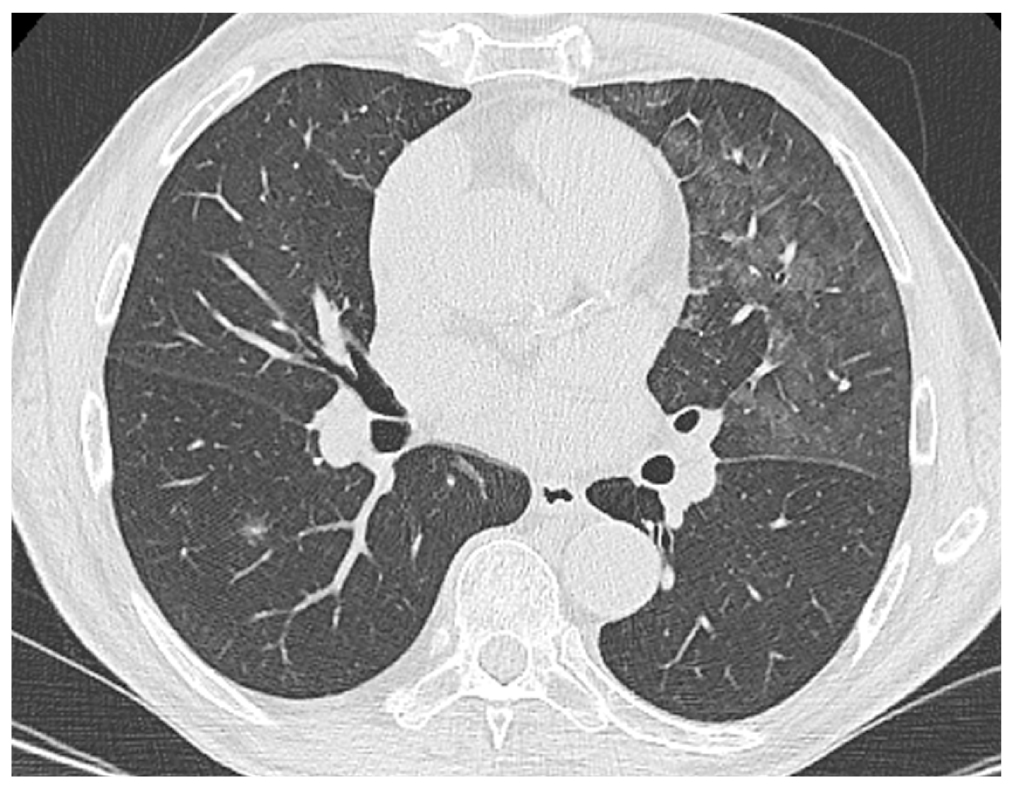

Несмотря на проводимое лечение, через 10 дней у пациента развился острый болевой синдром в поясничной области, в связи с чем повторно выполнена МРТ: на фоне сохраняющегося абсцесса выявлены признаки спондилодисцита на уровне L2–L3 (рис. 6). С учетом полученных данных было принято решение об очередном изменении антибактериальной терапии, направленной на лечение спондилодисцита.

Рис. 6. Тот же пациент: магнитно-резонансная томограмма поясничного отдела позвоночника: а — аксиальный срез в режиме Т2-FLAIR на уровне L2–L3; б — сагиттальный срез позвоночного столба в режиме T2-FLAIR; в — сагиттальный срез позвоночного столба в режиме STIR. Стрелкой указан абсцесс (а); контурами выделены абсцесс (б) и очаг спондилодисцита (в). / Fig. 6. The same patient: magnetic resonance imaging of the lumbar spine: а — axial slice in T2-FLAIR mode at the L2–L3 level; б — sagittal slice of the spinal column in T2-FLAIR mode; в — sagittal slice of the spinal column in STIR mode. Arrow indicates an abscess (а); abscess (б) and the spondylodiscitis (в) focus is outlined.